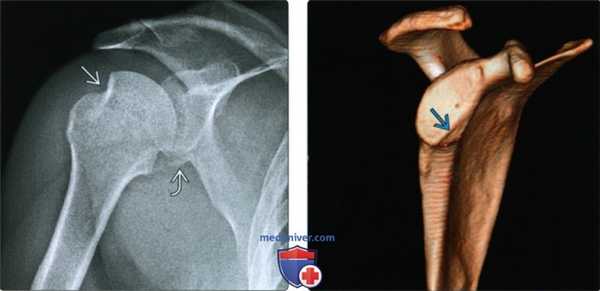

(Слева) Передне-задняя рентгенограмма, пациент после вправленного вывиха: перелом Хилла-Сакса заднелатеральной части головки плечевой кости и небольшой перелом Банкарта.

(Справа) На сагиттальной 3D КТ пациента с многократными передними вывихами в анамнезе и увеличивающейся нестабильностью определяется дефект в передненижнем крае суставной впадины. Дефект края суставной впадины в результате резорбции отломка Банкарта и/или механического износа края суставной впадины может появиться при повторных вывихах.